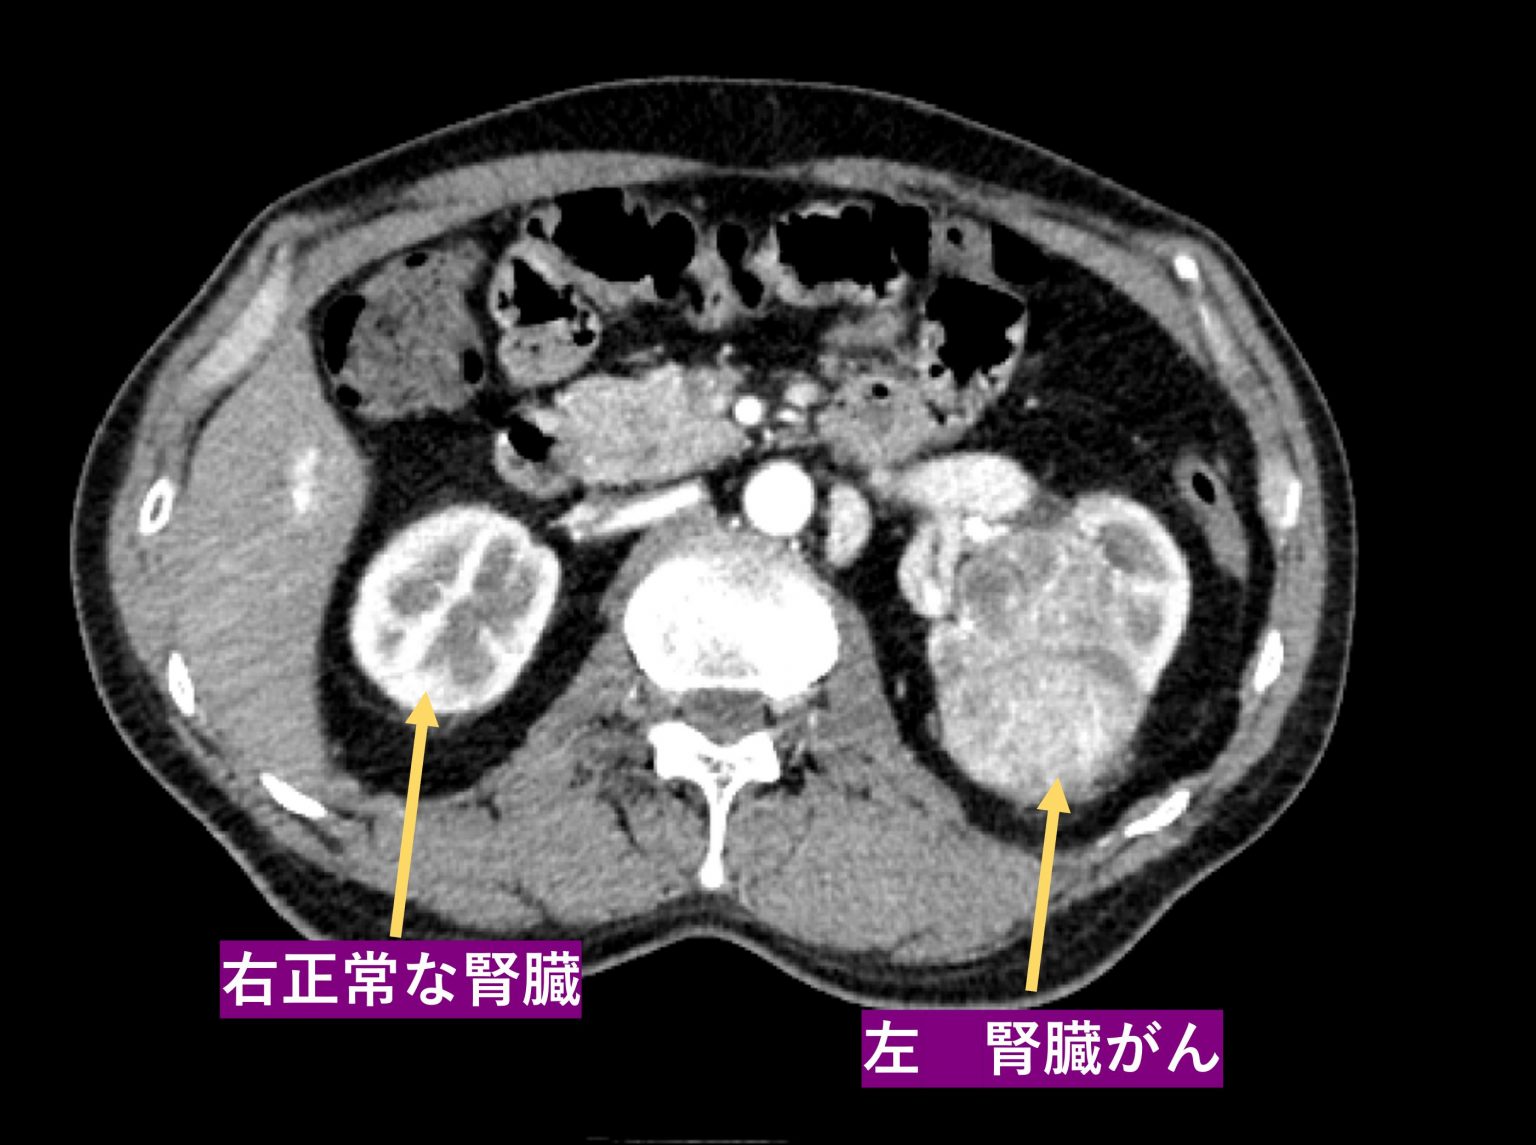

RCCは腎臓がんの最も一般的な形態です。

腎臓の特定の細胞が異常に成長し、発達するときに発症します。これらの細胞が発達すると、腎臓腫瘍が形成される可能性があります。

がんが増殖し続けると、がん細胞が体の他の部分に移動し、最終的にはさまざまな臓器に腫瘍を形成する可能性があります。これは転移性RCCと呼ばれます。